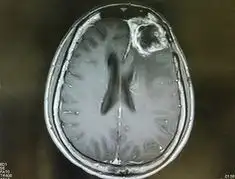

교모세포종의 진단은 주로 고해상도의 영상 진단 도구인 MRI 또는 CT를 통해 이루어집니다.

이러한 검사를 통해 종양의 위치, 크기 및 주변 조직과의 관계를 정확히 평가할 수 있습니다.

또한, 최종적인 진단을 위해서는 조직 검사가 필수적으로 수행됩니다.